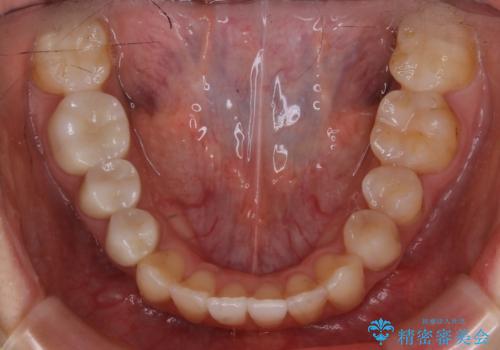

【非抜歯】歯を抜かずに歯列をコンパクトに!

- 前歯のガタつきと噛み合わせの改善を希望してご来院されました。

目立たない装置での矯正治療をとのことでインビザラインを用いた非抜歯矯正を行うこととなりました。

歯のガタつきをとるためのスペース作りの方法の一つにディスキング(IPR)という方法があります。

歯と歯の間を一ケ所あたり最大0.5mmまでの範囲内で削ることで歯自体が少し小さくなり、それにより作られるスペースを数ヶ所分合わせることで合計で数mmの大きなスペースが作れるという方法です。

当院ではなるべく歯の機能や見た目に影響の出ないよう、作業時に拡大鏡の使用や削るタイミングの微調整を行っています。